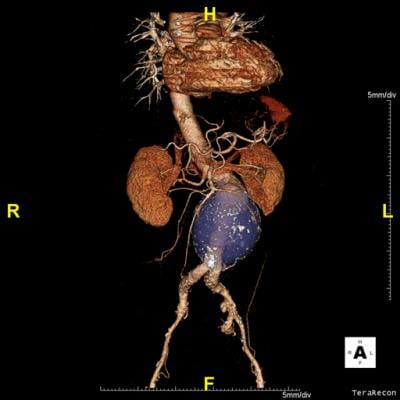

November 15, 2016 — TeraRecon, together with full-color 3-D printing cloud provider WhiteClouds, announced new technological and workflow process to print highly detailed models directly from the TeraRecon software. The new 3D Print Packs make online, cloud-based 3-D reconstruction and printing simple, fast and affordable.

Using the process, there is no need for a 3-D printer, third-party software or the use of large STL files. With a user-friendly workflow and zero startup costs, customers can quickly create high resolution and life-like anatomical models.

Still, 3-D printing has proven to be a powerful and useful tool, specifically in patient education, pre-surgical planning, oncology, implantable devices and more.

WhiteClouds also announced the launch of 3DyourSCAN, a life-size color printed, anatomical model of a patient's computed tomography (CT) or magnetic resonance imaging (MRI) scan designed to improve collaboration and education between physicians and patients.